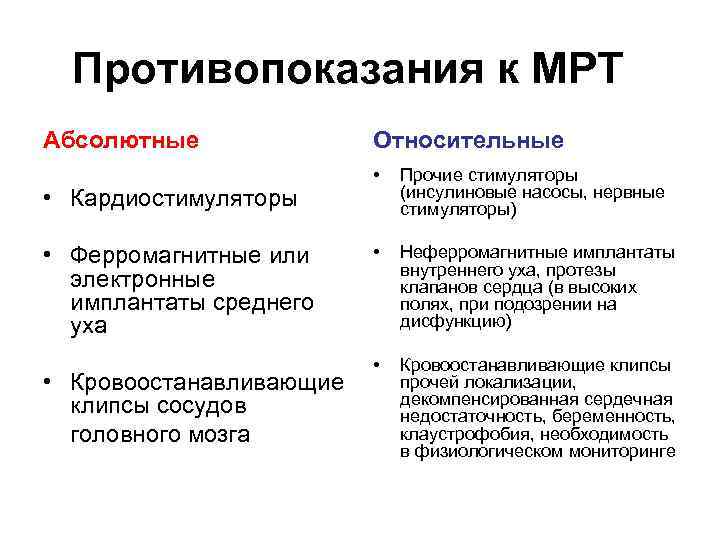

Противопоказания к МРТ Абсолютные • Кардиостимуляторы • Ферромагнитные или электронные имплантаты среднего уха • Кровоостанавливающие клипсы сосудов головного мозга Относительные • Прочие стимуляторы (инсулиновые насосы, нервные стимуляторы) • Неферромагнитные имплантаты внутреннего уха, протезы клапанов сердца (в высоких полях, при подозрении на дисфункцию) • Кровоостанавливающие клипсы прочей локализации, декомпенсированная сердечная недостаточность, беременность, клаустрофобия, необходимость в физиологическом мониторинге